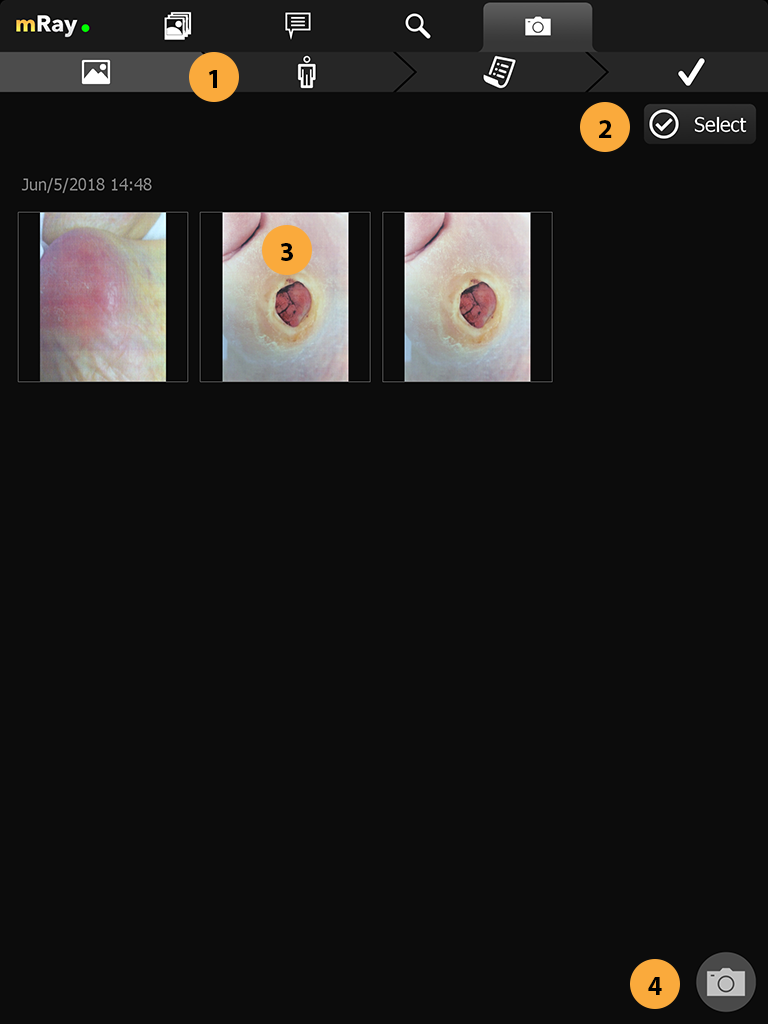

-

Neue Merkmale über Fotodokumentation Kamera hinzugefügt.